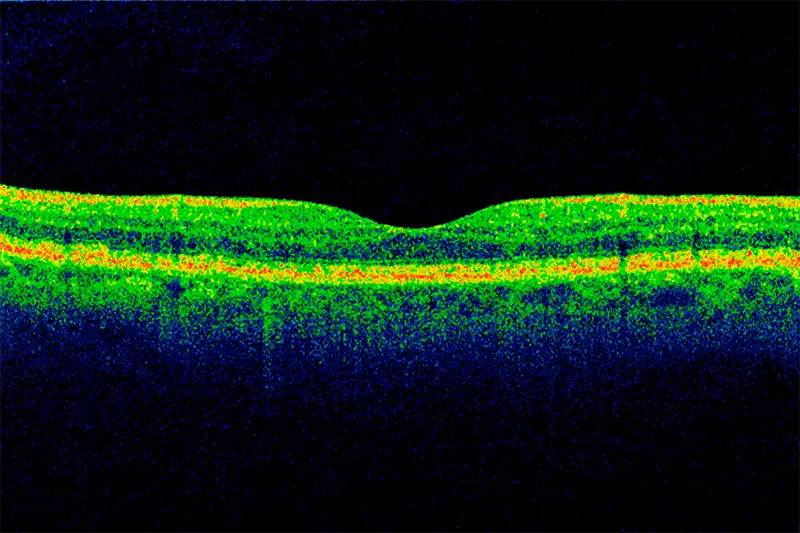

Optical coherence tomography scan of a section through the macula of the retina

Optical coherence tomography scan of a section through the macula of the retina. The volume of high-quality imagery that is collected in ophthalmology provides rich data for AI models.

“Ophthalmology is a very imaging-driven and data-driven field. We’ve accumulated very large databases here, some of which contain data on hundreds of thousands of visual field tests and optical coherence tomography images collected over many years. We know this is critical for AI,” Dr. Liebmann says. “Over time, we’ve been able to apply algorithms to this data, which has evolved into machine learning and artificial intelligence. Our strong academic partnerships are helping us advance and develop this technology into ways to assist clinicians in practice.”